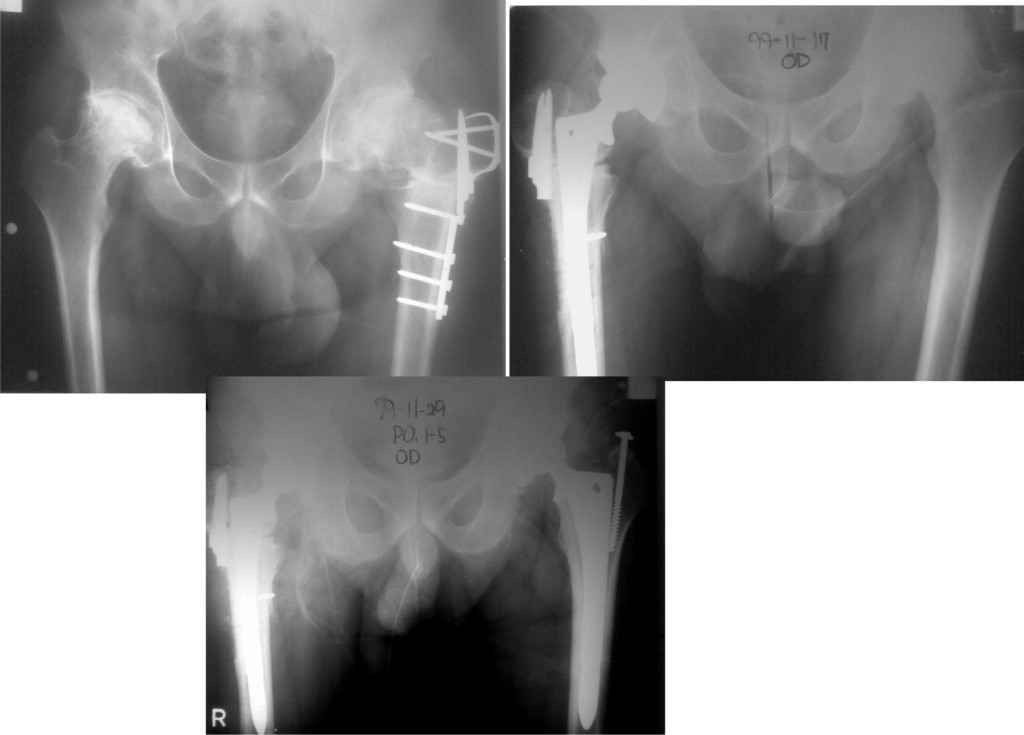

У меня опыт по эндопротезированию совсем не большой.Еще 5 лет тому назад у нас в городе не было протезирования. Во вложении снимки одного больного из нашего города. который оперировался в 1999 году в Южной Корее. разница по времени замены второго сустава 11 дней. Больной по настоящее время ходит без проблем, особых жалоб не предявляет, весит он 98 кг. Может быть есть смысл подождать, по наблюдать а оперировать никогда не поэдно.